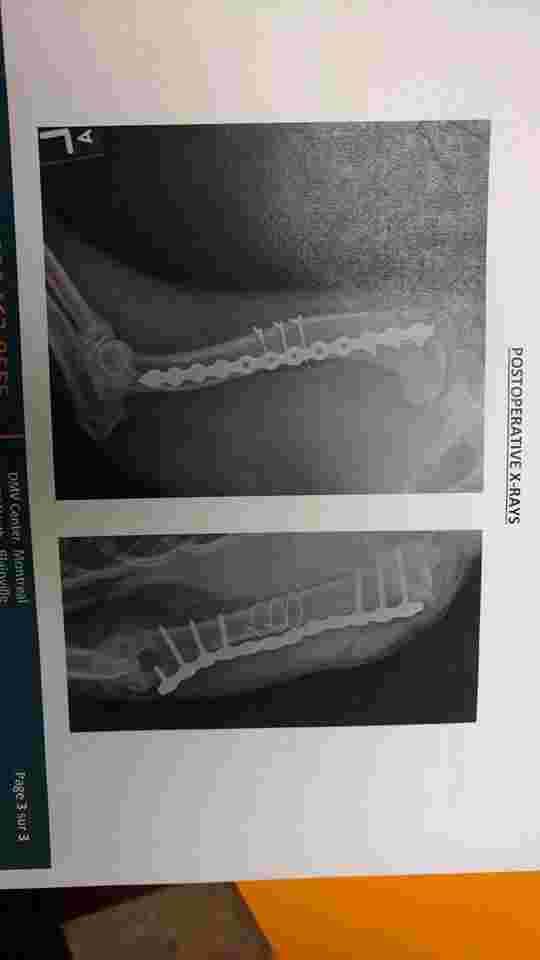

So my dog broke her leg back in February and needed surgery to put a plate and screws in. She ended up breaking 3 of the screws and when we took her to the vet the other day they said we should get the plate and remaining screws removed because it can cause a lot of problems later on. So I'm wondering roughly how long would recovery time be and what can I expect later on in her life? Will her bad leg be okay without the plate supporting It?

Poor Dakota. She has been through a lot for such a young girl. The plate is necessary to keep the bone stable while it heals. Once the bone has healed, the plate is no longer needed, but we often leave it in place as long as it isn't causing a problem to avoid a second surgery. The recovery after removing the plate and screws will depend on what her x-rays look like right now. Sometimes it is only a couple of weeks and sometimes it is 8-10 weeks. So, follow your vet's recommendation on that. Hopefully this will be Dakota's last surgery and she can get back to her normal self soon! Good luck! I hope that was helpful. Thanks for using Petco Pet Education Center, formerly Petcoach.